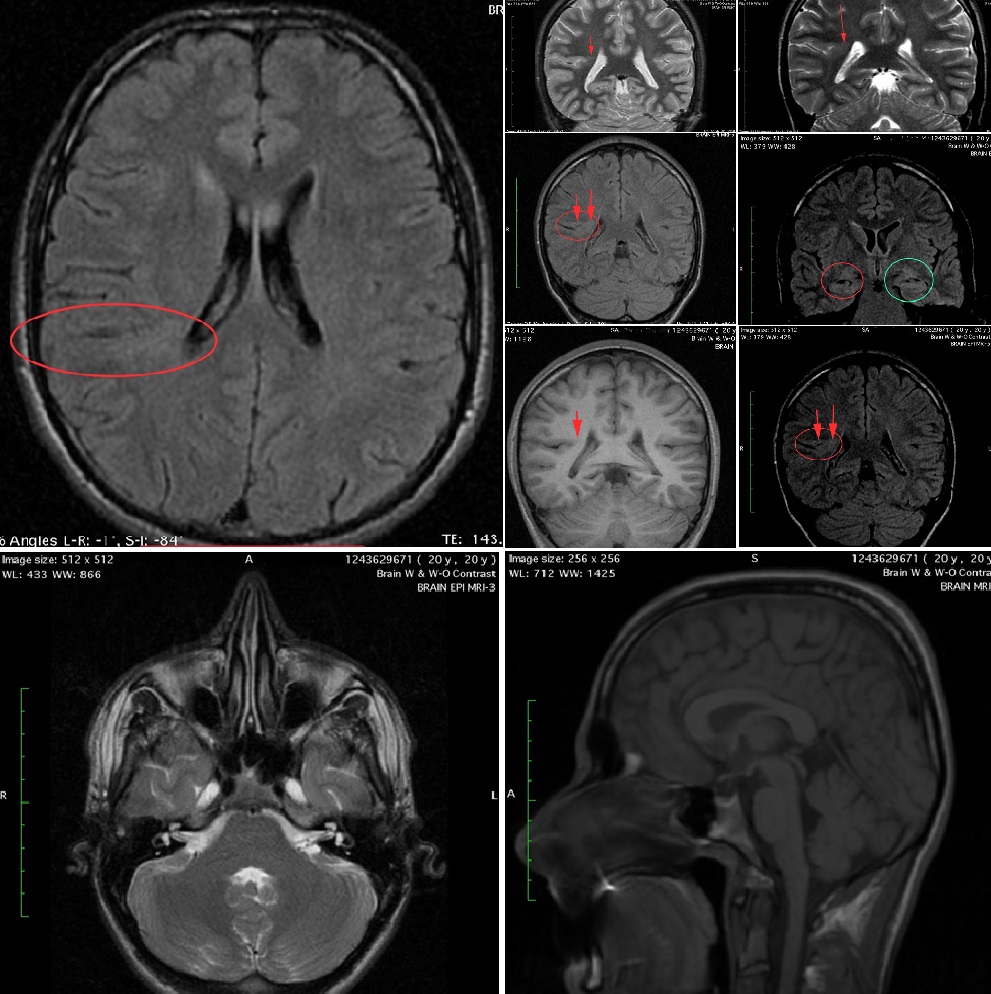

Epilepsy since childhood, curable?

See the good news to a 20 year-old male, with intractable epilepsy since childhood.